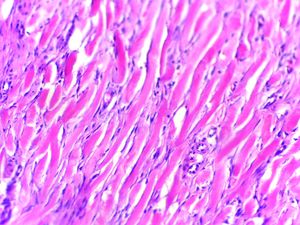

6. 병리조직학적 특징

켈로이드는 조직학적으로 비정형 섬유아세포가 과도하게 세포외 기질 성분, 특히 콜라겐, 피브로넥틴, 엘라스틴, 프로테오글리칸을 침착시켜 특징지어지는 섬유성 종양이다. 일반적으로 켈로이드는 상대적으로 무세포 중심과 병변의 깊은 진피 부분에 결절을 형성하는 두껍고 풍부한 콜라겐 묶음을 포함한다.[9]

진피에서 피하 조직에 걸쳐 유리질의 굵은 콜라겐 섬유 다발이 종횡으로 뒤섞여 증식하는 패턴이 특징적이다. 콜라겐 섬유 다발 사이에는 방추형 섬유아세포가 분포한다. 방추 세포는 면역조직화학적으로 비멘틴 양성이며, 증례에 따라서는 평활근원성 액틴이 양성이어서 근섬유아세포로의 분화를 시사한다. 비후성 반흔과의 감별은 유리질 콜라겐 섬유 다발의 양을 참고하지만, 반드시 감별이 용이한 것은 아니다. 안면 피부에 발생하는 경화성 섬유종(sclerotic fibroma), 안면 섬유성 구진(fibrous papule of the face)과의 감별에 어려움을 겪는 경우도 있어, 임상의로부터의 정보 제공이 정확한 진단에 필수적이다.